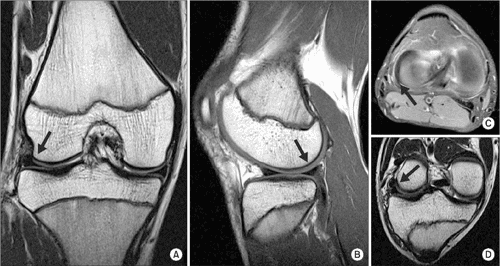

Meniscal tear essay image This image representes meniscal tear essay.

MRI is the exam of choice because it is the only modality that directly visualizes the meniscus and separate soft-tissue joint components. Arthrocentesis indicated a blinking effusion, which was probably a event of trauma.